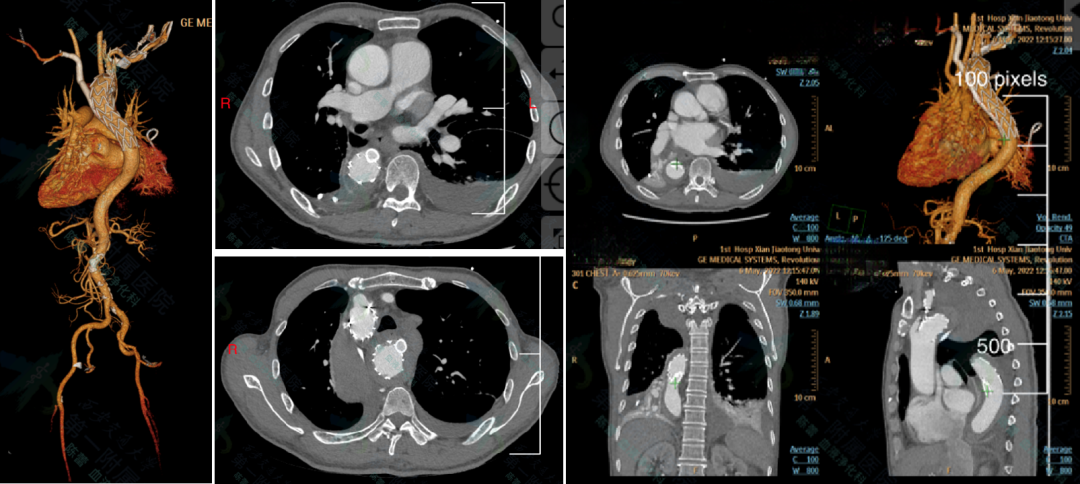

★Case 3 主动脉破裂+右位弓+ 迷走左锁骨下动脉+ Kommerell憩室

治疗难点:主动脉濒临破裂、解剖复杂

手术策略:Castor支架迅速封堵破口+潜望镜技术重建双侧锁骨下动脉

结果:快速稳定血流,患者转危为安

术后一月复查CTA,Castor支架及潜望镜通畅,假腔隔绝良好,纵膈及胸腔血肿吸收。

术后一年复查CTA,潜望镜远端出现Ib型内漏